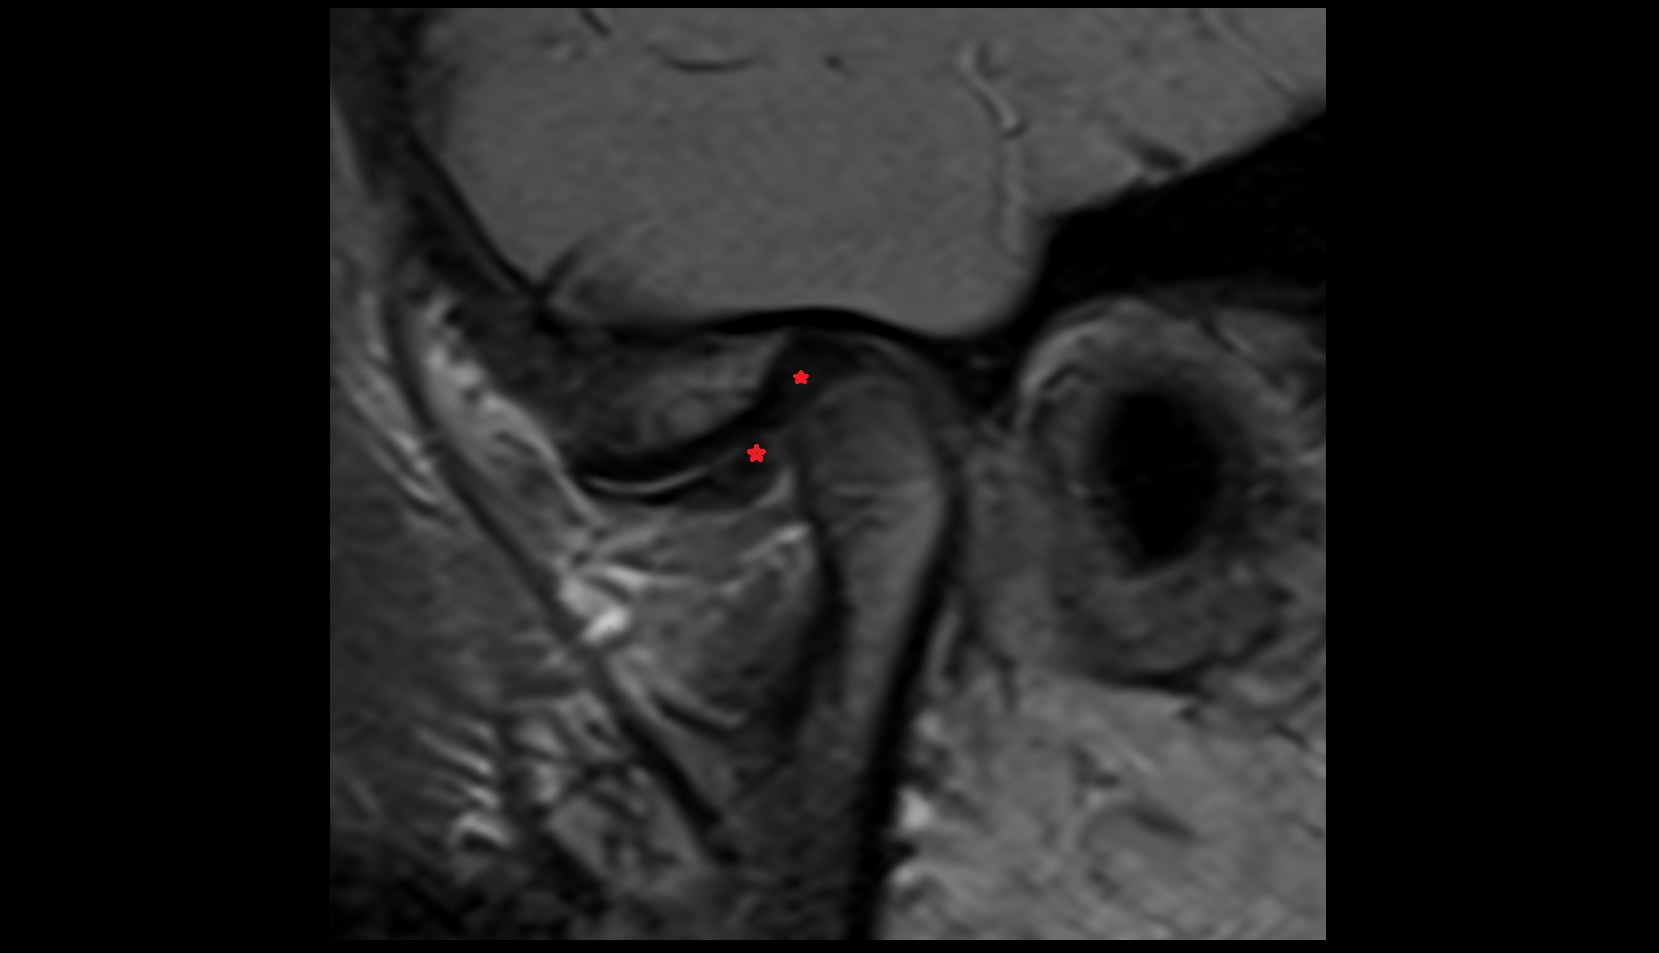

- Articular disc of temporomandibular joint

- Intermediate zone of articular disc

- Temporomandibular joint

- Mandibular condyle

- Mandibular fossa